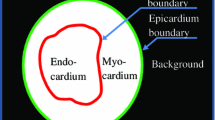

The sliding motion along the boundaries of discontinuous regions has been actively studied in B-spline free-form deformation framework. This study focusses on the sliding motion for a velocity field-based 3D+t registration. The discontinuity of the tangent direction guides the deformation of the object region, and a separate control of two regions provides a better registration accuracy. The sliding motion under the velocity field-based transformation is conducted under the \(\alpha\)-Rényi entropy estimator using a minimum spanning tree (MST) topology. Moreover, a new topology changing method of the MST is proposed. The topology change is performed as follows: inserting random noise, constructing the MST, and removing random noise while preserving a local connection consistency of the MST. This random noise process (RNP) prevents the \(\alpha\)-Rényi entropy-based registration from degrading in sliding motion, because the RNP creates a small disturbance around special locations. Experiments were performed using two publicly available datasets: the DIR-Lab dataset, which consists of 4D pulmonary computed tomography (CT) images, and a benchmarking framework dataset for cardiac 3D ultrasound. For the 4D pulmonary CT images, RNP produced a significantly improved result for the original MST with sliding motion (p<0.05). For the cardiac 3D ultrasound dataset, only a discontinuity-based registration indicated activity of the RNP. In contrast, the single MST without sliding motion did not show any improvement. These experiments proved the effectiveness of the RNP for sliding motion.

Tobon-Gomez C, De Craene M, Mcleod K, Tautz L, Shi W, Hennemuth A, Prakosa A, Wang, H, Carr-White G, Kapetanakis S, et al: Benchmarking framework for myocardial tracking and deformation algorithms: An open access database. Medical image analysis 17(6), 632–648,2013